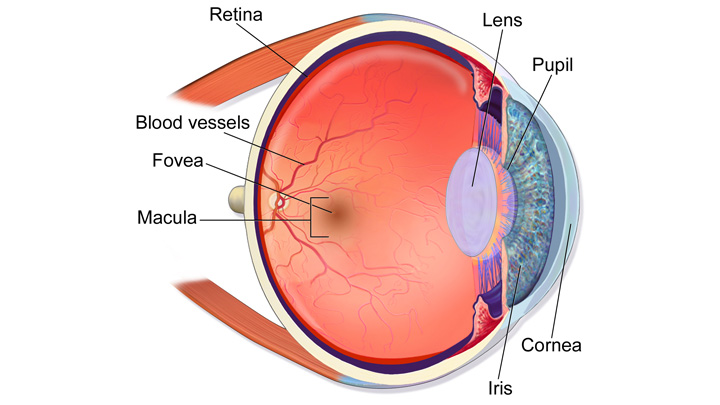

Изображения и анатомия сетчатки глаза

Раздел: Визуальный дайджест